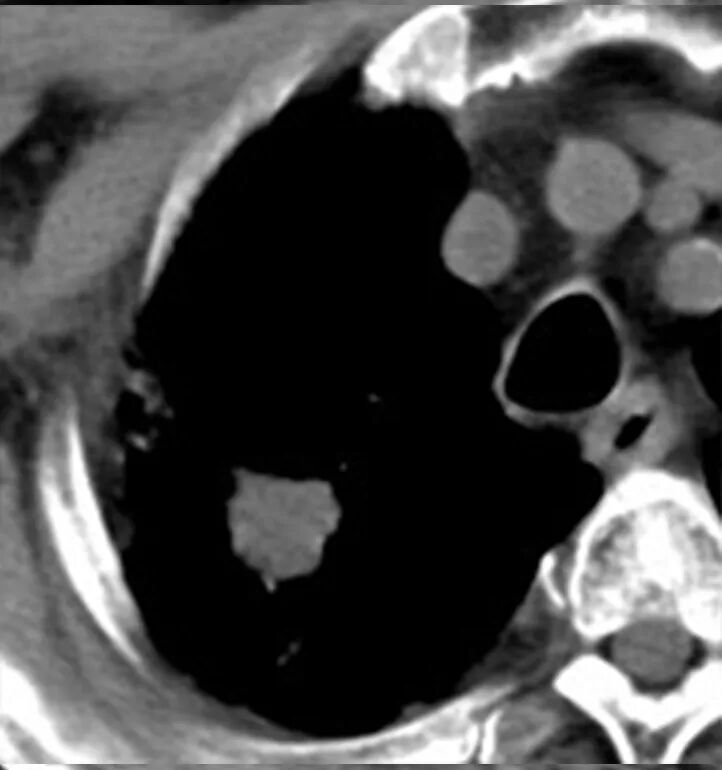

经过王剑飞和肿瘤中心MDT团队的认真讨论,确诊王大伯为右肺恶性肿瘤。“那要手术么?”家属着急地询问着。“大伯80多岁了,心肺功能也不好,手术治疗不耐受的,还是考虑局部治疗,也就是放射治疗”,王剑飞耐心解释着。 经过考虑,大伯和家属都接受了放射治疗的建议。放疗中心副主任刘文君、主治医师阮龙飞为王大伯详细制定了右肺上叶肿块根治性放疗的治疗方案。很快,王大伯便正式开始了治疗。 一年过去了,王大伯早已结束了治疗,而他的定期复查结果令人欣喜——右肺上叶肿块持续缩小,现在已经几乎消失了! “还好听医生话还算及时!”每次看到复查报告,王大伯都十分高兴,一再感谢肿瘤科团队的帮助与悉心照料。 王剑飞提醒市民:发现肿瘤并不是最可怕的,可怕的是不重视或不配合治疗,这是医生最无能为力的局面。 治疗前 治疗结束 治疗结束后2月 治疗结束后10月